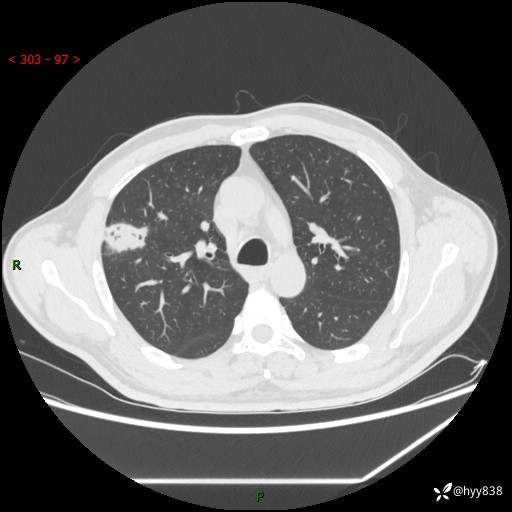

现病史:患者2天前体检完善胸部CT提示:右上肺团块影,炎症可能,肿瘤性病变不除外,冠状动脉钙化,无咳嗽、咳痰,无寒战发热,无恶心、呕吐等其他特殊不适,未予以特殊治疗,现为明确病变性质来我院就诊,门诊以“肺肿物性质待查”收入我科。 起病以来,患者精神、饮食、睡眠可,大小便正常,体力体重较前无明显变化。

胸部CT平扫+增强